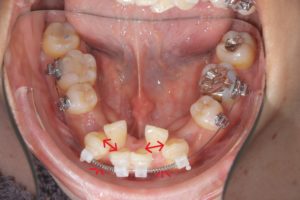

第一小臼歯抜歯後1カ月経過。

中切歯と犬歯の間にオープンコイルを入れ

側切歯のスペース作り開始。

抜歯後5カ月経過。側切歯にブラケット装着。

抜歯後10カ月経過。舌側にリンガルボタンを装着。

パワーチェーンを使ってスペース閉鎖中。

前歯にスペースが開かないように、犬歯~犬歯を連続結紮。

このような重度叢生の場合も抜歯して作った

スペースを利用しレベリングをするケースもあります。